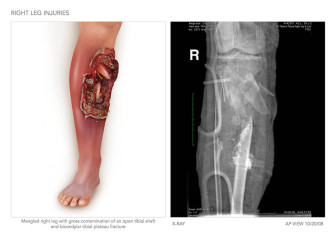

Summary of Left Leg Injuries